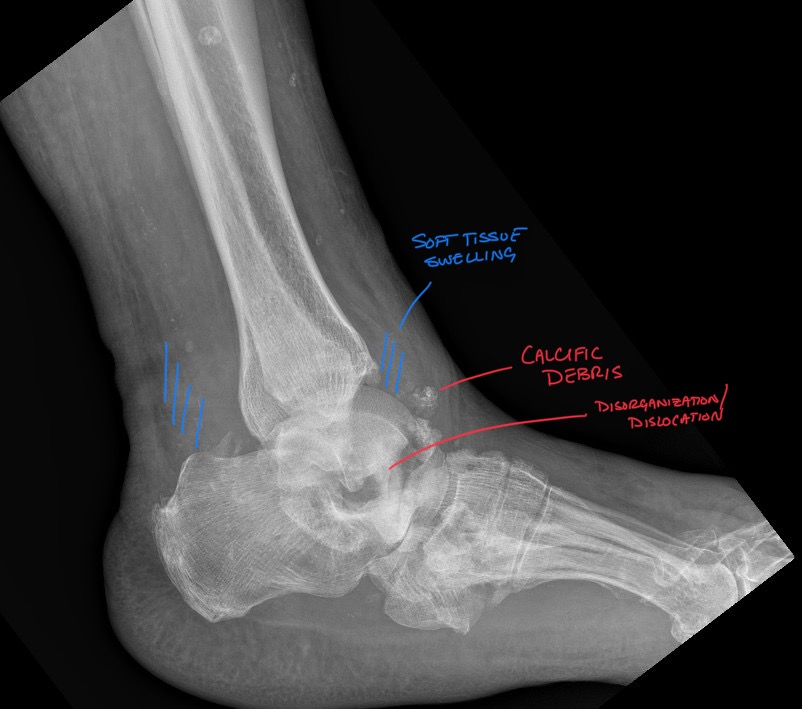

Charcot arthropathy: Professional Imaging Consultants Guide to Joint Destruction

Charcot arthropathy: Professional Imaging Consultants Guide to Joint Destruction Clinical History Is that “hot, swollen ankle” in your diabetic patient